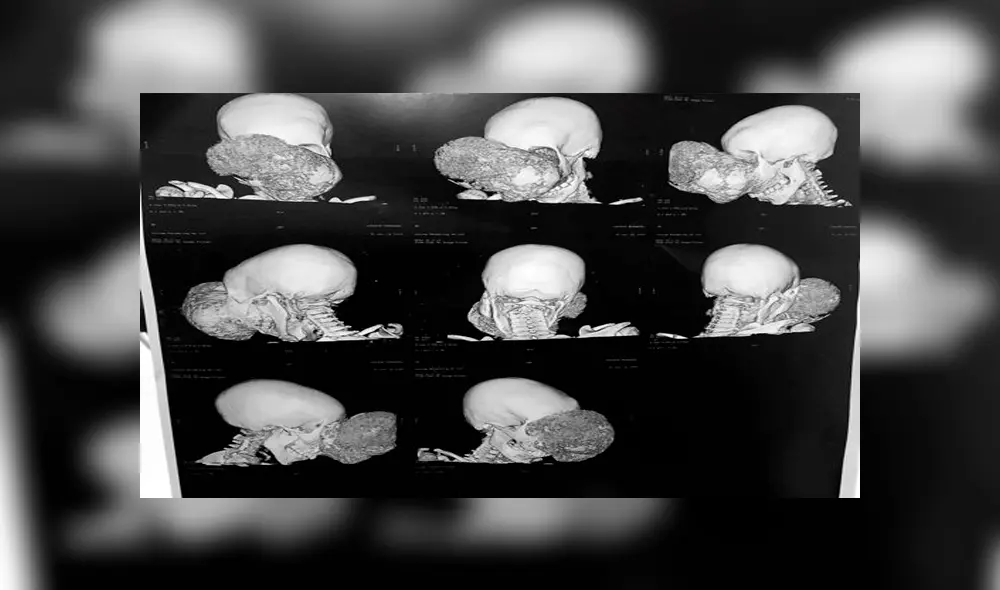

El doctor español, Pedro Cavadas, realizó una operación muy complicada a un niño africano de 10 años, el cual tenía un tumor más grande que su cabeza.

El cirujano explicó que el tumor craneofacial era no maligno, pero que si no era tratado a tiempo, el paciente podría haber muerto en muy malas condiciones y en poco tiempo.

El pequeño, identificado como Emmanuel, asistió a una clínica en el Congo para luego ser derivado en la Fundación Cavadas. Fue en este lugar donde le dijeron que dentro de su cráneo había un fibroma osificante gigante. Esto le impedía hablar y mirar.

“No tenía vida, ese crío habría durado dos telediarios, estaba condenado a una muerte en muy malas condiciones y relativamente pronto”, manifestó el doctor para la agencia EFE. “Debería hacer una vida completamente normal. Ahora, por lo menos, tiene cara”.